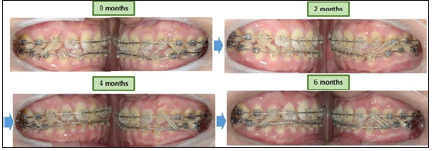

Establishment of stable interdigitation with intermaxillary elastics

In this case, canine relationship and good interdigitation were achieved within 6 months (Figure 12).